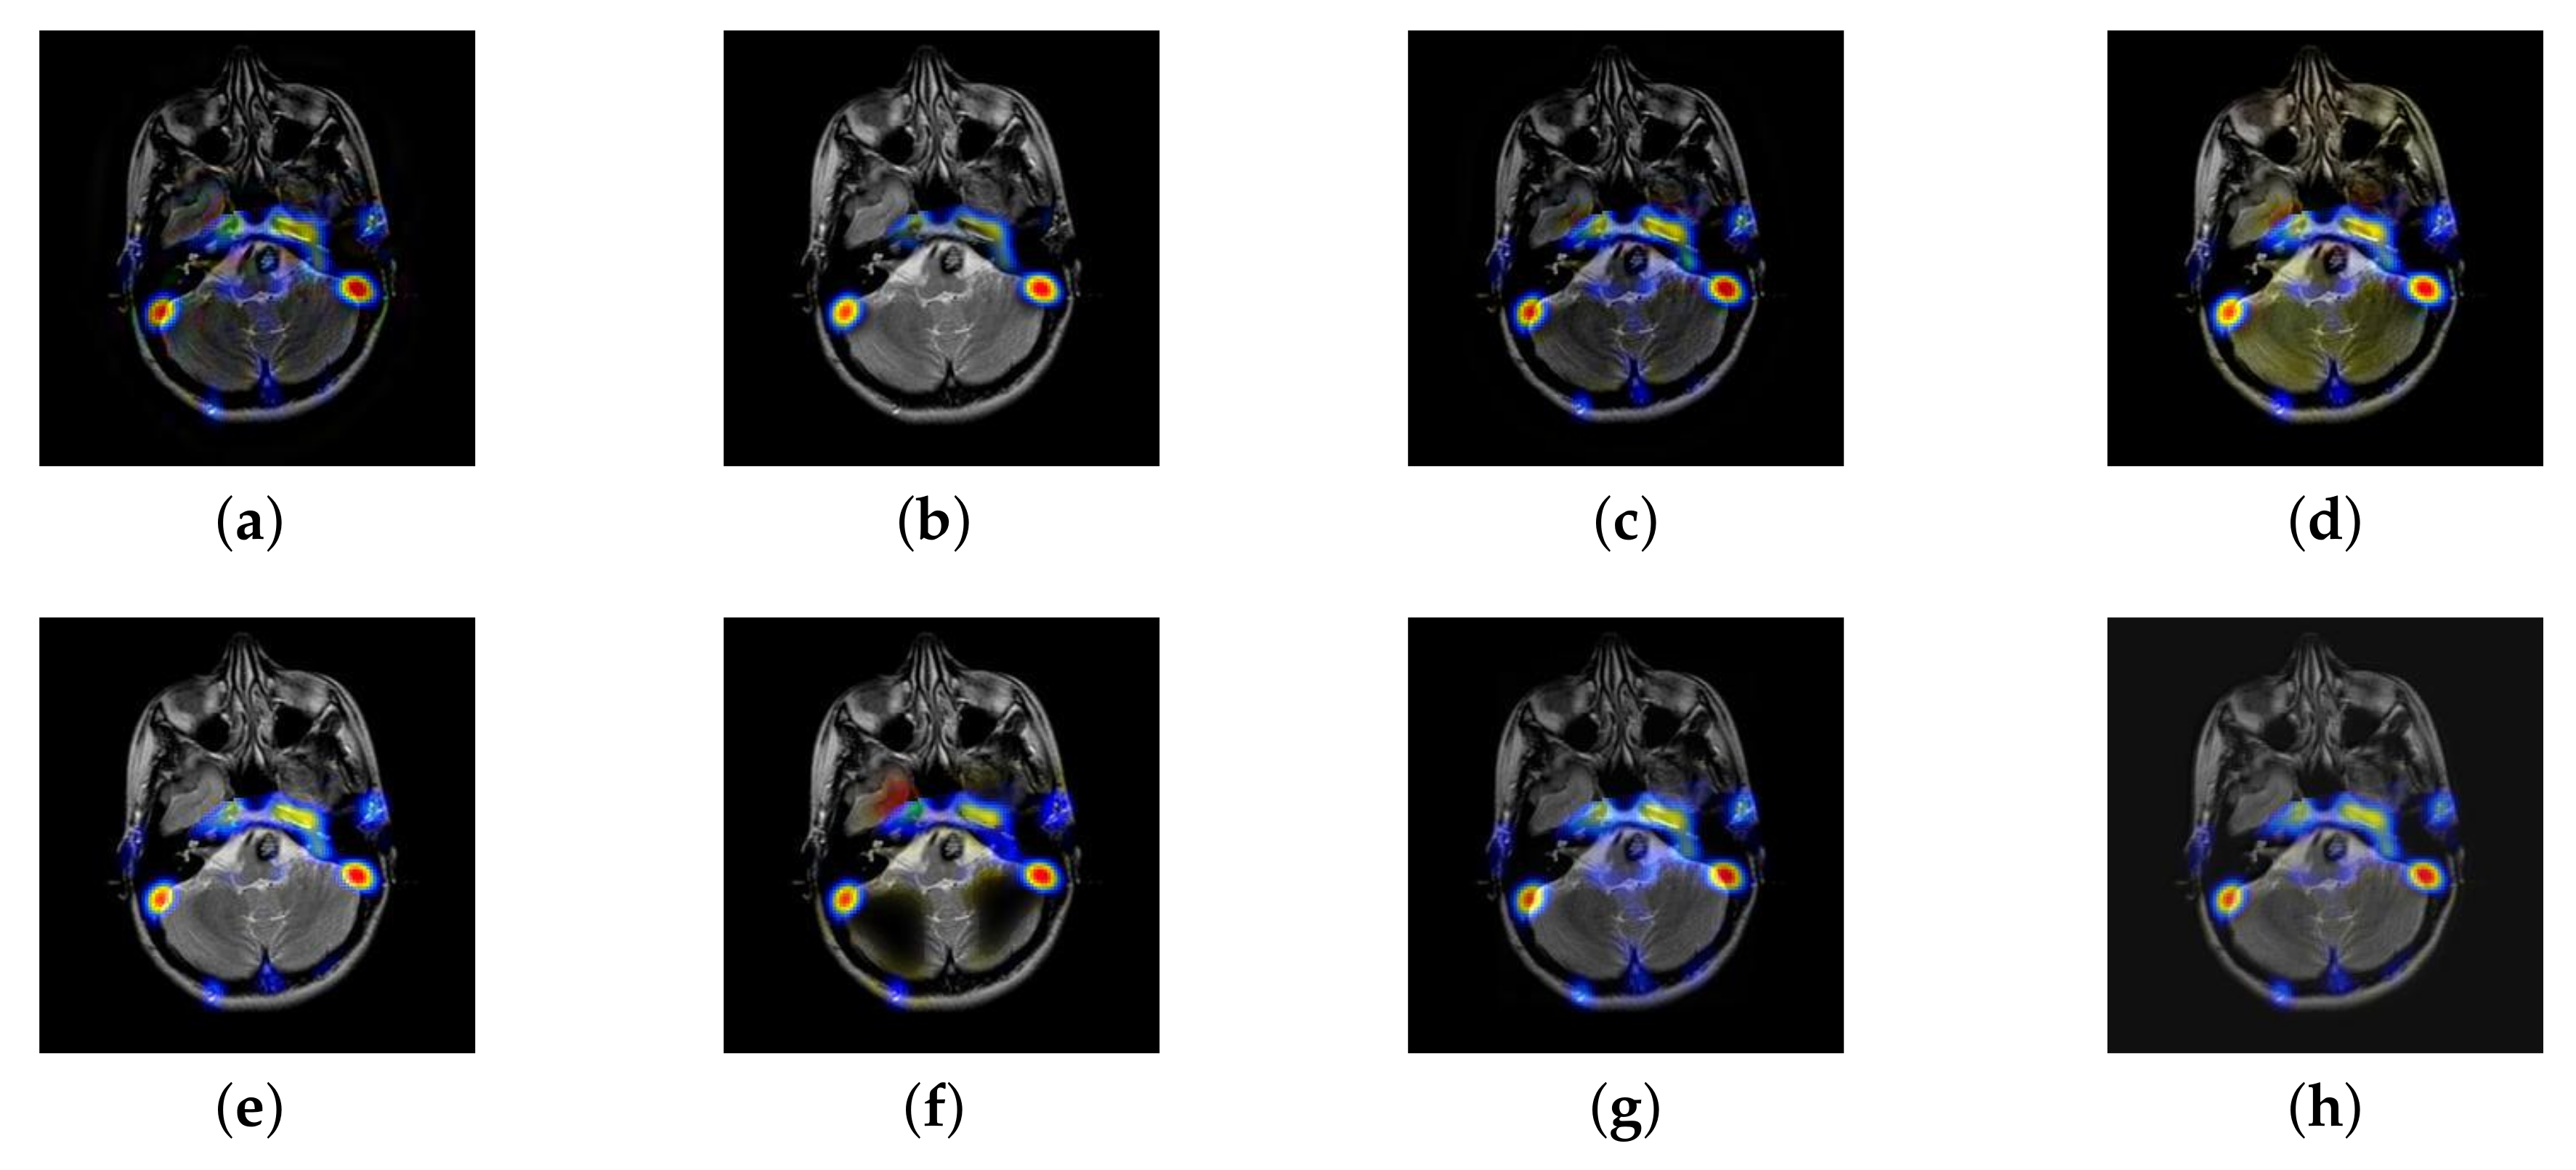

4.4. The Fusion of MRI-CBF

Cerebral blood flow diagram (CBF), which indicates the amount of blood flow in brain tissue with color. Red, yellow, green, blue, and black successively indicate the amount of blood flow from more to less. It is mainly used to detect the blood flow supply condition, elasticity, tension, and peripheral resistance. However, with the development of medical science, CBF image is often inferior in the diagnosis of brain diseases due to its lack of structural information. Therefore, MRI which is good at expressing structural information, is introduced to fuse in the current trend of brain medicine.

In this section, there are four image sets to fuse, each containing a MRI image and its corresponding CBF image in Figure 41. In Figure 42, Figure 43, Figure 44 and Figure 45, it can be seen that the structural information of fusion images obtained by our algorithm is complete. The color is not distorted, and the spectral features are natural. The fusion image based on DTCWT and NSCT algorithm have high color fidelity but less structural information. Other algorithms, such as IGM, LPSR, and FusionCNN, only focus on the structural information of the MRI image and ignore the color information of the fused image. Although the image structure information obtained by DDcGAN fusion algorithm is relatively complete, the edge of color information is not clear, which has a great influence on image contrast.

Figure 42.

Fused medical images obtained by different algorithms (Figure 41a,b): (a) DTCWT, (b) GFF, (c) NSCT, (d) LPSR, (e) IGM, (f) FusionCNN, (g) DDcGAN, and (h) FusionNet.

Figure 43.

Fused medical images obtained by different algorithms (Figure 41c,d): (a) DTCWT, (b) GFF, (c) NSCT, (d) LPSR, (e) IGM, (f) FusionCNN, (g) DDcGAN, and (h) FusionNet.

Figure 44.

Fused medical images obtained by different algorithms (Figure 41e,f): (a) DTCWT, (b) GFF, (c) NSCT, (d) LPSR, (e) IGM, (f) FusionCNN, (g) DDcGAN, and (h) FusionNet.

Figure 45.

Fused medical images obtained by different algorithms (Figure 41g,h): (a) DTCWT, (b) GFF, (c) NSCT, (d) LPSR, (e) IGM, (f) FusionCNN, (g) DDcGAN, and (h) FusionNet.

The averaged subjective scores of MRI-CBF fusion images obtained by the above methods are shown from Figure 46 and Figure 47. Our fusion algorithm has obvious advantages in EN, FMI, SSIM, , , and AG from Figure 48, Figure 49, Figure 50, Figure 51, Figure 52, Figure 53, Figure 54, Figure 55, Figure 56 and Figure 57. Other metrics are inferior to those of FusionCNN, GFF, and LPSR fusion algorithm. However, as we have mentioned before, there may be inconsistency between subjective indicators and objective indicators, but this does not affect the assessment of image quality.